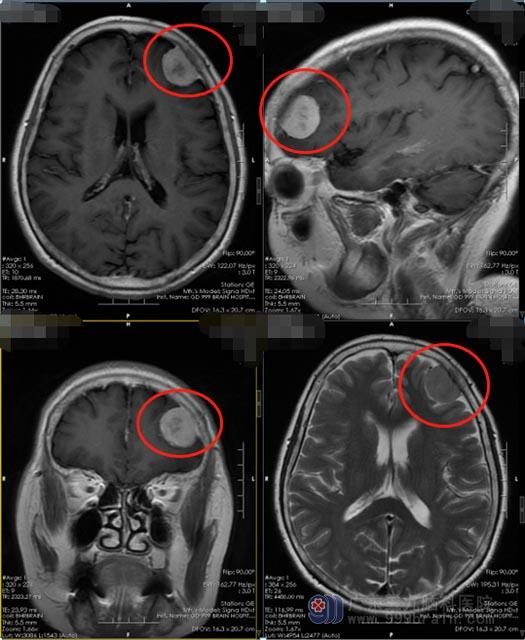

近两天来,邹奶奶出现头晕,感觉持续性的天旋地转伴走路不稳。这时候,她才意识到问题有点严重了,当地医院头颅CT检查提示“左侧额部占位性病变,性质待查”;在广东三九脑科医院进一步MR检查显示:左侧额部颅骨内板下占位性病变,脑膜瘤可能性大。